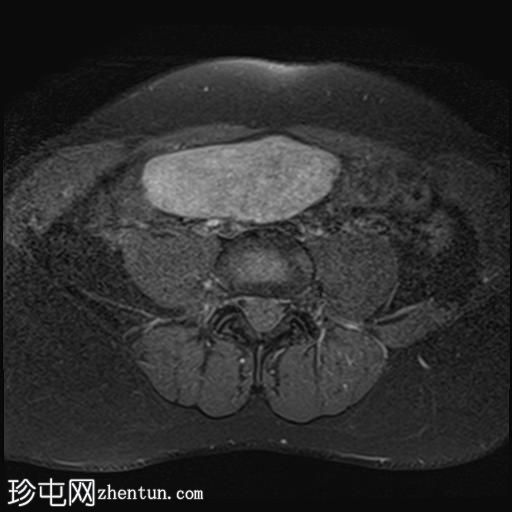

轴位

T2加权像

盆腔内可见多个边界清晰的肿块:

其中一个位于子宫上方,T2加权像呈中等信号,中心区域呈高信号,增强T1脂肪抑制像未见强化。右侧卵巢增大,增厚的血管蒂扭曲,未见强化,轴位和矢状位T2加权像均显示清晰。

另一个位于子宫后窝,T2加权像呈中等信号,增强扫描显示明显强化。

轻度腹腔积液